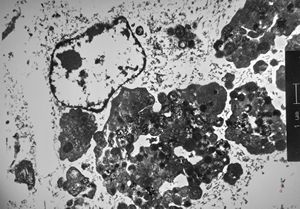

M, | dystrophic calcification and malaric pigment - brain